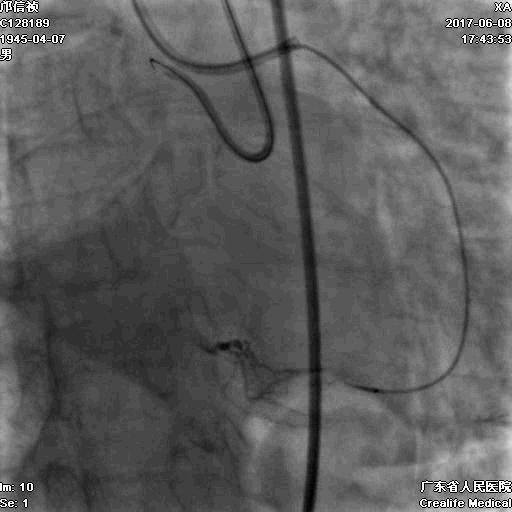

冠脉造影

基本资料

Syntax score 37.5